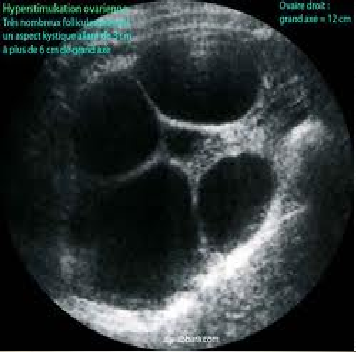

Les hyper-stimulations ovariennes (qui provoquent fréquemment des douleurs abdominales) peuvent nécessiter parfois une hospitalisation.